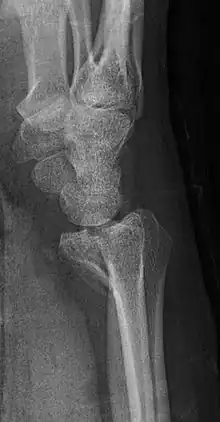

A Barton's fracture is a type of wrist injury where there is a broken bone associated with a dislocated bone in the wrist, typically occurring after falling on top of a bent wrist.[1] It is an intra-articular fracture of the distal radius with dislocation of the radiocarpal joint.[2]

There exist two types of Barton's fracture – dorsal[3] and palmar, the latter being more common. The Barton's fracture is caused by a fall on an extended and pronated wrist increasing carpal compression force on the dorsal rim. Intra-articular component distinguishes this fracture from a Smith's or a Colles' fracture. Treatment of this fracture is usually done by open reduction and internal fixation with a plate and screws, but occasionally the fracture can be treated conservatively.[4]